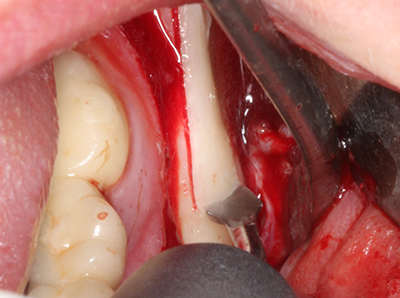

En la extracción de bloques óseos la piezocirugía también presenta ventajas adicionales: Además de la alta precisión en la osteotomía que ya se ha descrito antes, se ha comprobado que el uso de los delgados insertos de sierra resulta especialmente cuidadosas con el hueso. Frente a esto, sobre todo cuando se usan las fresas de Lindemann, cabe esperar pérdidas en la extracción significativamente más altas debido al mayor grosor de la parte frontal del cabezal (Lakshmiganthan, Gokulanathan et al. 2012). La separación basal que se necesita en particular en los injertos de bloque extraídos de forma retromolar se ve facilitada mediante sierras perpendiculares especialmente previstas a tal fin, lo que permite considerar que la cirugía piezoeléctrica es un procedimiento preciso y seguro para la obtención de bloques de hueso en el área retromolar (Happe 2007) (fig. 1-12).

Fig. 3: La separación basal del bloque se ve facilitada con piezas dotadas de una angulación especial.

Fig. 4: Con la rasqueta ósea se obtienen virutas adicionales de hueso autógeno.

Fig. 5: Comprobación de las dimensiones del bloque en la zona de recepción.